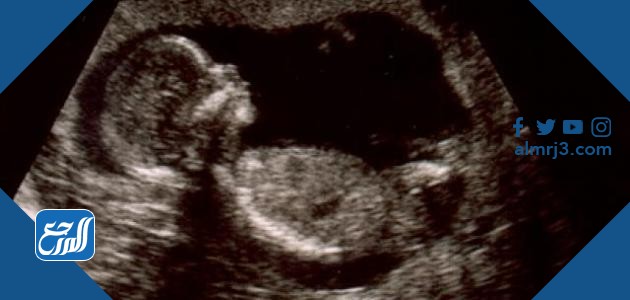

الفحص بالسونار

تعد طريقة الفحص بالسونار أو الموجات الصوتية من أشهر الطرق وأكثرها انتشارًا والتي من خلالها يمكن التعرف على نوع الجنين بقدر كبير من الدقة. والفحص بالسونار حتى يكون أكثر دقة فإنه يتم إجراؤه في الثلث الثاني من الحمل أي ما بين الأسبوع السادس عشر والأسبوع العشرين من الحمل. وتعتمد هذه الطريقة على تمييز الأعضاء التناسلية للجنين والتي تكون واضحة خلال هذه الفترة، فيكون العضو الذكري للجنين واضح، كما تكون الأعضاء التناسلية للأنثى أيضًا قد اكتمل نموها. ولكن الفحص بالسونار قد لا يكون دقيق بنسبة 100%، حيث قد يختلط على الطبيب في بعض الأحيان التفرقة بين الحبل السري الذي قد يظهر على شكل العضو الذكري، فيعتقد أن الحمل بالذكر وهو في الحقيقة أنثى.[1]